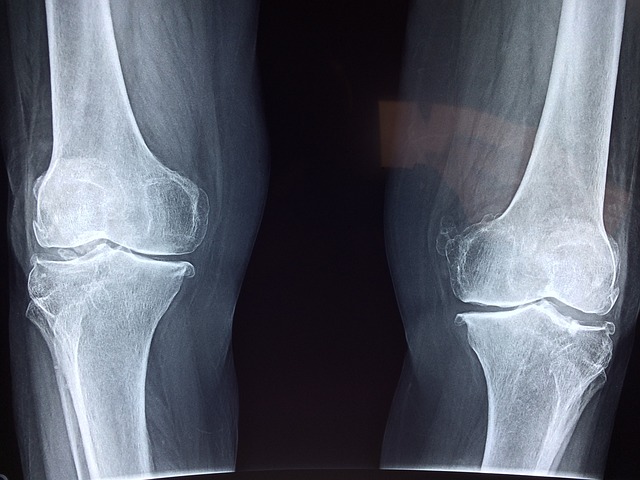

4-1 골관절염 관절 통증 치료에 도움

퇴행성관절염은 우리가 피해갈 수 없는 질환입니다. 앞서 말씀드렸다시피 움직이지 않고 가만히 있지 않는 이상 관절은 계속 닳고 있습니다.

콘드로이친은 얇고 닳기 쉬운 연골의 마모를 방지하고 연골의 부피 유지에 기여하여 관절염의 통증을 완화하는 데 도움을 줄 수 있습니다.

한 연구에 따르면 무릎 통증 환자를 대상으로 콘드로이친을 4개월간 섭취하게 한 결과 관절 통증이 43% 감소하고 보행 능력이 개선되었다. 섭취 후 6개월 뒤에는 관절의 경직 시간이 줄어든 것으로 나타났습니다.

4-7 연골세포 보호

콘드로이친은 연골세포 분해를 억제시켜 연골세포를 보호해주며 역할을 유지시켜 준다고 합니다. 연골은 노화가 진행될수록 나이가 들어갈수록 크기가 줄어들거나, 끊어질 수 있는데 콘드로이친이 그 스펀치같은 역할을 하여 연골 속 수분을 매워 연골이 부드럽고 유연하게 유지할 수 있도록 도와줍니다.